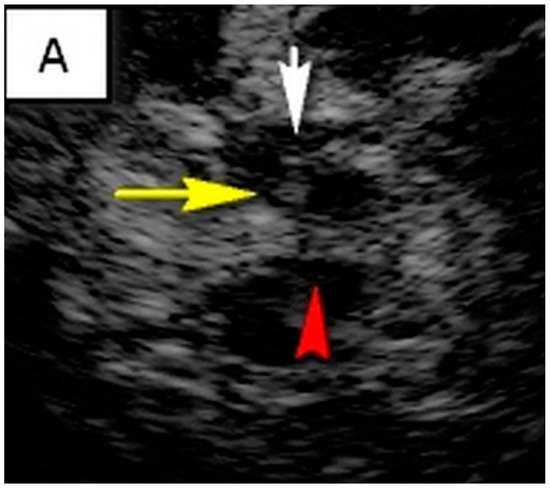

TCS characteristics of interest in our study are illustrated in Table 2. The control subjects consisted of 31 healthy controls, of which there was a slight female predominance (54.8%). The mean age of control subjects was 45.7 ± 11.6 years. The brainstem raphe was discontinued in 33.8% of patients. The SN hyperechogenicity was identified in 79.7% of patients, which represented a significant pathological finding, Figure 1. Third ventricle enlargement (over 6 mm) was present in 79.7% of patients, which can be attributed to gross (whole) brain atrophy, Figure 1. The fourth ventricle was enlarged in 45.9% of patients, which can directly be attributed to the atrophy of the cerebellum and its reduction in volume. The hyperechogenicity of other brain structures, such as the NR, the lentiform nucleus (NL) and the dentate nucleus (ND), is also illustrated in Table 2. We found a statistically significant difference in the hyperechogenicity of SN on the left and the sum quantitively, as well as in the frequencies of hyperintensity between patients with degenerative ataxias and the control subjects (p < 0.05). We have also found statistical significance in the difference between these two groups in the domain of the III and IV ventricles (p < 0.01). Results of mesencephalic atrophy are also presented in Table 2.

Figure 1.

(A) Butterfly-shaped hypoechogenic mesencephalic brainstem insonation level. Normal echogenicity of the brainstem raphe (highly hyperechogenic continuous line, same echogenicity as red nucleus; red arrow); dotted like highly hyperechogenic red nucleus (NR) (yellow arrow); normal echogenicity of substantia nigra (SN) (white arrow). (B) Butterfly-shaped hypoechogenic mesencephalic brainstem insonation level. Hypoechogenic interrupted raphe (red arrow); hyperechogenic substantia nigra (SN) (blurred yellow area, above 0.19 cm2). (C) Third ventricle level insonation depicted as hyperechogenic parallel lines. Normal diameter of the third ventricle (inner borders marked with red line). (D) Third ventricle level insonation depicted as hyperechogenic parallel lines. Dilatated third ventricle (12 mm, inner borders marked with white asterisk).